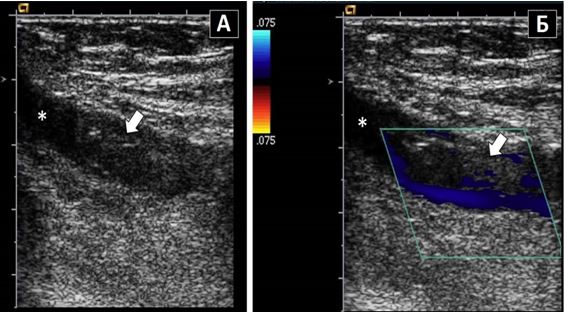

Аневризма аорти під контролем ультразвуку

Що ефективніше для скринінгу торакальних аневризм КТ чи УЗД?